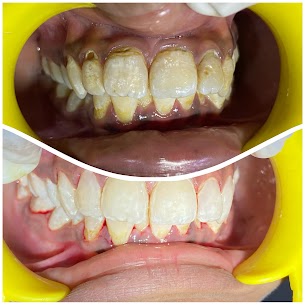

Comprehensive Periodontal Treatment

- INFO:

Month-long treatment for 55-year-old combining flap surgery, bridges, and implants